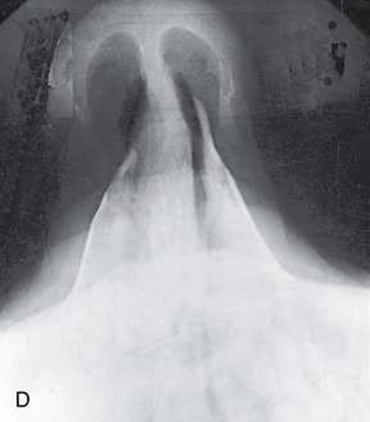

Incidência SUBMENTOVERTEX – Ossos  zigomátitos

Aprenda agora a fazer a Incidência  SUBMENTOVERTEX – Ossos  zigomátitos

• Levantar o queixo, hiperestender o pescoço até que a LIOM  esteja paralela ao RI.

• Apoiar a cabeça no ápice craniano.

• Alinhar o PSM perpenditularmente à linha média da grade ou mesa/superfície do dispositivo de imagem vertical, evitando qualquer inclinação ou rotação.

• Alinhar o RC perpendicularmente ao RI.

• Centralizar o RC a meio caminho entre os arcos zigomátitos, ao nível de aproximadamente 4 cm abaixo da sínfise mandibular.

• Centralizar o RI ao RC, com plano do RI paralelo ao da LIOM.

• Fraturas do arco zigomático.

• Processos neoplásticos ou inflamatórios.